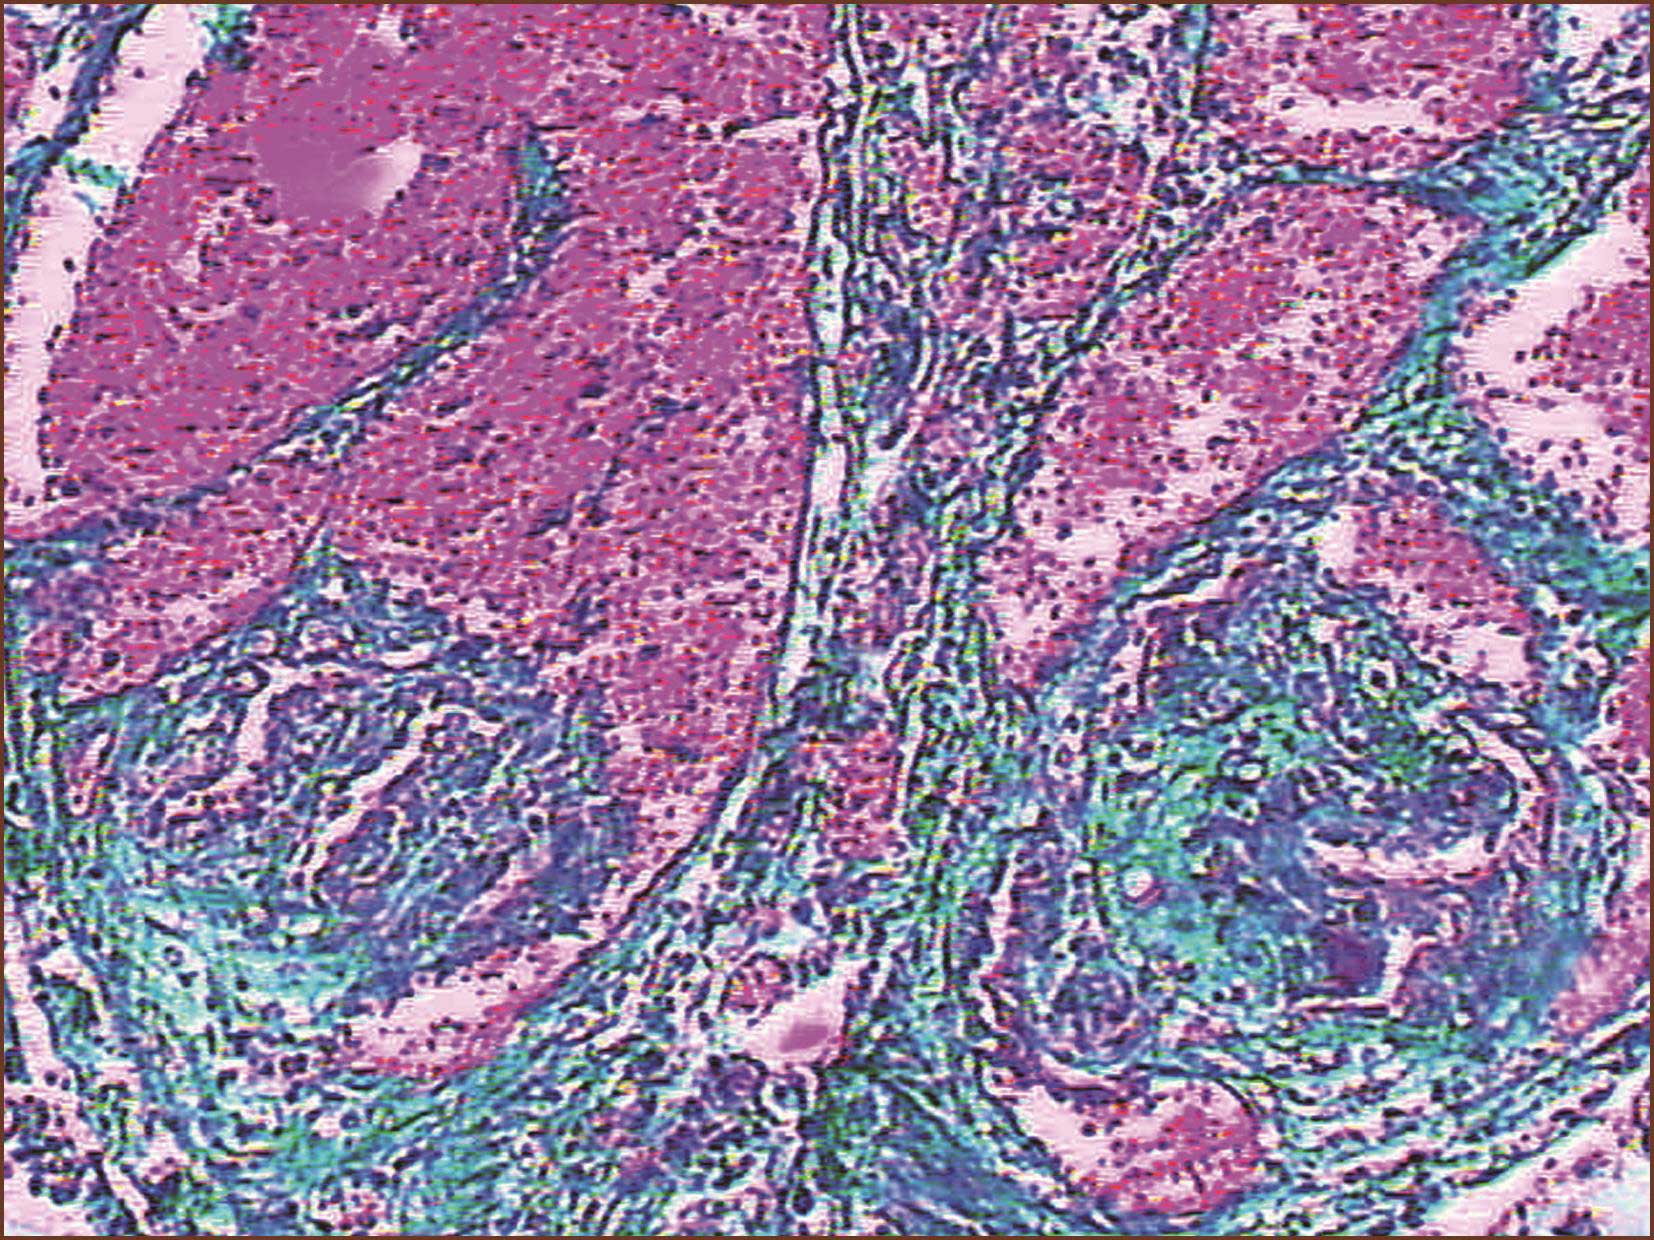

(七)肺静脉阻塞病

肺静脉阻塞病(pulmonary veno-occlusive disease,PVOD),以前称肺阻塞性静脉病(pulmonary occlusive venopathy)。此种肺动脉高压很少见。临床表现类似IPAH,主要靠病理组织学确诊。病理组织学表现为广泛的大小不一的肺细小静脉纤维化阻塞,阻塞的纤维组织可以是松散的水肿样,含有不同种细胞;或为静脉内致密的无细胞性纤维化。病变很少累及大的肺静脉。静脉病变或为少数偏心性,或为多发偏心性纤维化-来自血栓的机化。PVOD累及的细小静脉中层可见弹力纤维和平滑肌细胞增多而增厚、出现双层弹力板-被称为静脉动脉化(arterialization)。以上病变有助于与被动性肺静脉高压区别。在慢性被动性肺静脉高压,其静脉、毛细血管充血,原发于心脏瓣膜病或大肺静脉疾病。另外,PVOD的肺小静脉壁和附近肺泡壁存在钙化物质包绕的弹力纤维和由此引起的异物巨细胞反应,也是除外被动性肺静脉高压的组织形态之一,但这是非特异性的。当遇到间质性肺病或肺气肿的静脉病变时,这种钙化反应病变也可作为识别肺静脉阻塞病的辅助条件。肺细小动脉结构改建约见于50%的PVOD患者。

国际肺动脉高圧分类中称为与左心疾病相关的肺动脉高压(pulmonary hypertension associated with left heart diseases),亦有称静脉型或称慢性被动性(毛细血管阻力性)肺动脉高压,凡累及左心房、左心室、二尖瓣、主动脉瓣的各种疾病,各种原因引起的慢性左心衰竭、左心疾病,如二尖瓣、主动脉瓣狭窄、肺静脉病、左心房黏液瘤、三房心、晚期高血压病、冠心病、心肌病、二尖瓣替换术后的机械瓣失灵、左心房血栓或左心房肿瘤阻塞等,均可引起静脉型肺动脉高压。其病理特征是病变累及肺静脉,也累及肺动脉(图3-1-19)。其中静脉改变比动脉性肺动脉高压的肺静脉病变的发生早而重。肺小静脉、小动脉、毛细血管高度充血。静脉型肺动脉高压可产生肺细、小静脉中层肥厚、静脉 “动脉化”和内膜纤维化,常伴发肺泡间质充血、纤维化及含铁血黄素沉着。肺泡腔有多量含铁血黄素吞噬细胞(图3-1-20)即心力衰竭细胞,肺细小动脉也可产生中层肥厚(提示有PH),内膜纤维化;但未见有丛状病变的报道,也很少见肺动脉坏死或动脉炎症反应。此型与动脉性肺动脉高压不同处,还有肺动脉、静脉病变具有区域性差别:如风湿性心脏病二尖瓣病变患者,其肺动脉、静脉改变在肺底部比肺尖部明显,这种差异与肺下部流体静水压高有关。静脉型肺动脉高压的病变分级标准近似动脉型的Ⅰ、Ⅱ、Ⅲ级改变,既累及静脉,也累及动脉。而动脉性肺动脉高压以sPH动脉病变先发生并更明显,静脉病变少而轻。我们在1例风湿性二尖瓣病的尸检肺组织,发现在高度充血的肺间质内有多灶性肺微血管(细小静脉和毛细血管)瘤样增生。但其内皮细胞未见核分裂象。此种微血管增生可能为慢性严重肺血管淤血的反应性增生。

图3-1-19 肺小静脉充血,内膜明显纤维化增厚致管腔狭窄(ET+VG, ×200)